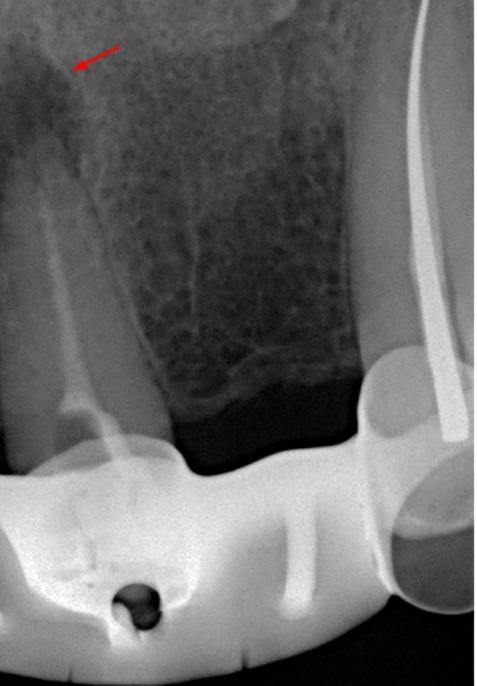

Выявлена болезненность при перкуссии и пальпации в области 21 зуба. Зуб не реагирует на термические раздражители. Результаты пародонтологического обследования в пределах нормы, рентгенологическое обследование выявило радиолюцентную зону в области верхушки корня (снимки 1, 2).

Диагноз: Острый апикальный периодонтит.

В связи с наличием у пациента жалоб и клинических симптомов принято решение о проведении ревизии корневого канала 21 зуба. Проведена терапия с помощью гидроокиси кальция в течении 4-х недель (снимок 3). Пломбировка канала гуттаперчей и корневым герметиком.